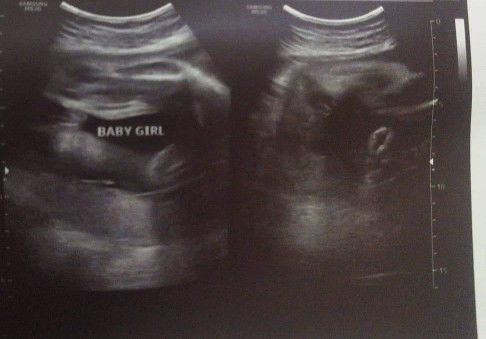

sandwich daw po itchura pag baby girl😅 pag boy makita mo daw may nakalawit😅

yes baby girl po. ganyan din utz ng sakin😊